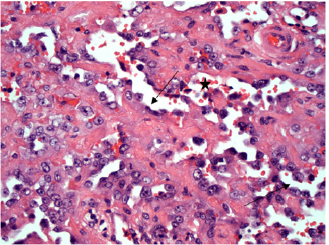

In the five horses diagnosed with conjunctival haemangiosarcoma, the histopathology findings confirmed the presence of a clearly vasoformative neoplasm in each case with the neoplastic endothelial cells either lining blood-filled vascular channels and/or forming solid nests (Fig. 3). Multiple lymphonodular aggregates or lymphoid follicles were commonly interspersed throughout the neoplastic infiltrate.

Fig. 3. H&E photomicrograph (400× magnification) of case 1 conjunctival haemangiosarcoma from the third eyelid of a horse. Irregular blood-filled vascular channels (star) formed by the tumour and lined by pleomorphic neoplastic endothelial cells (arrows).

Moderate to marked cellular pleomorphism and nuclear atypia were seen in all cases. Mitoses per 10HPF (2.73 mm2), varied from 3 to 34 per HPF, with case 4 displaying the highest number of mitoses and the only case with metastatic spread (Fig. 4). Solar elastosis was seen in five cases (Fig. 5).